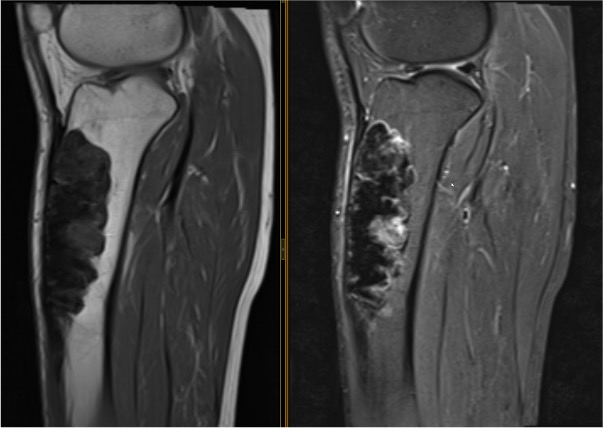

MRI

Khanna et al Skeletal Radiol 2008

- 24 cases of OFD / adamantinoma

- adamantinomas tend to be larger / cortical destruction / complete marrow involvement